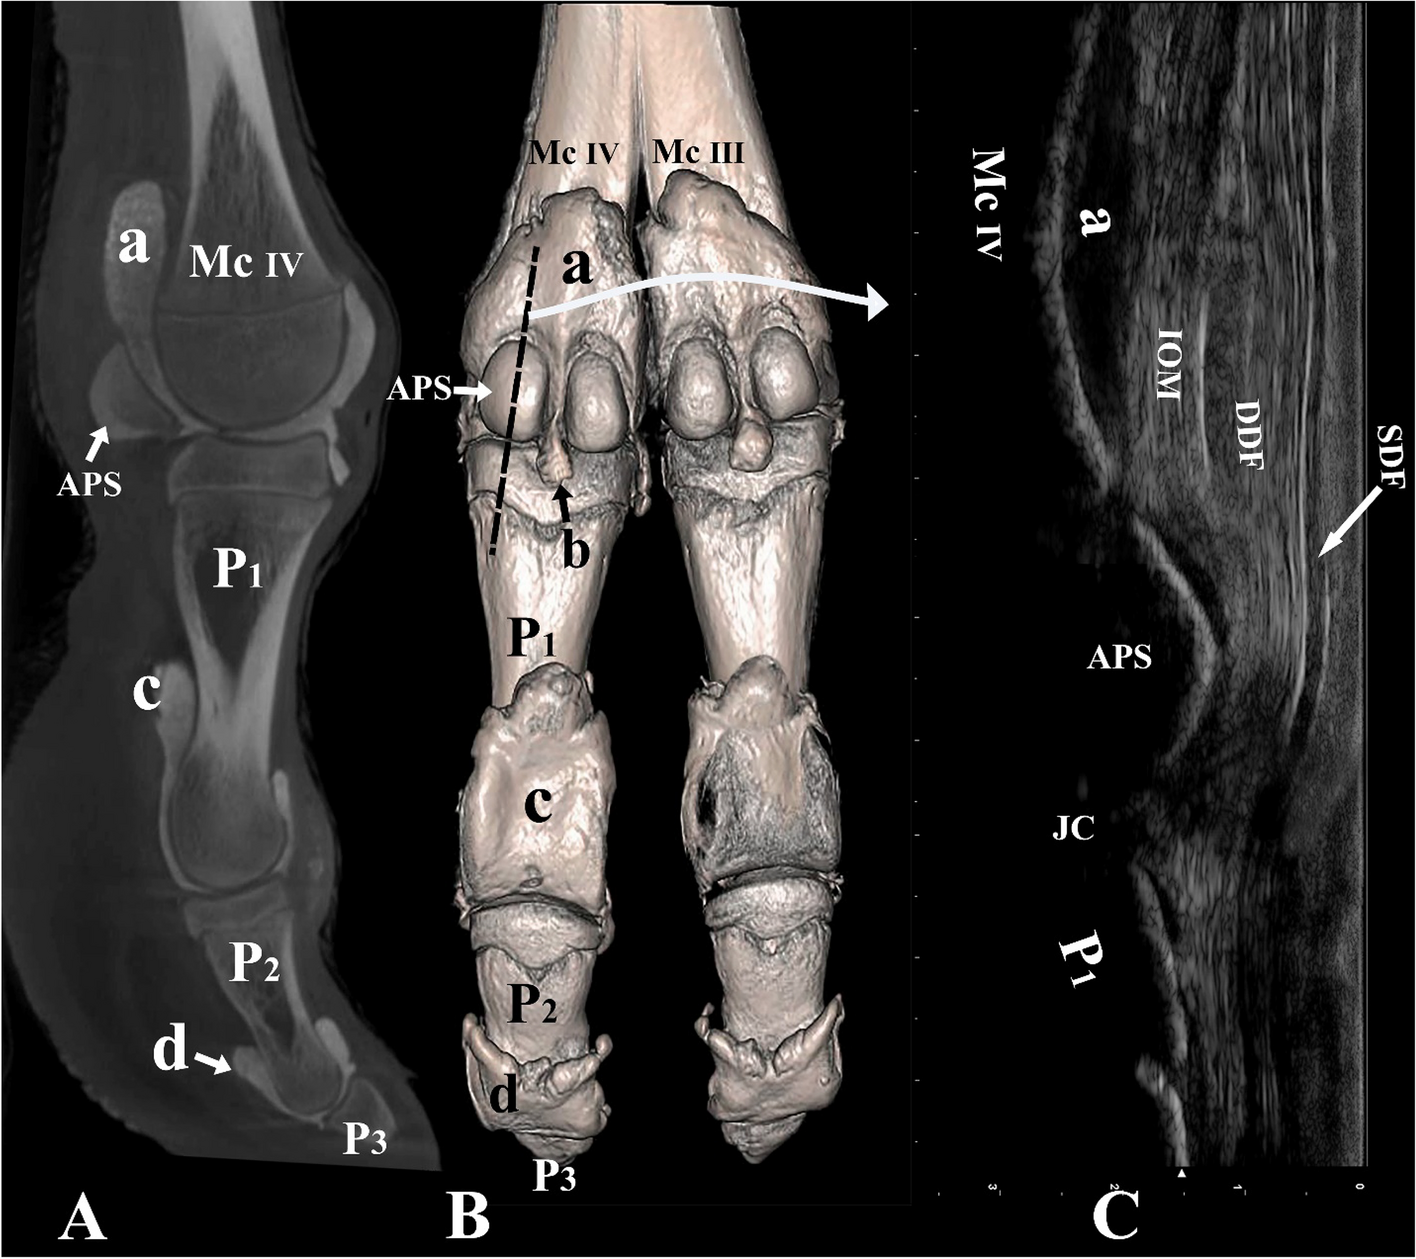

Figure 7

From: Arthrocentesis approaches to the phalangeal joints of the one humped camel (Camelus dromedarius)

Palmar and lateral view of the left distal forelimb and digit IV. (A) Sagittal plane CT image; (B) three-dimensional reconstruction (the black dotted line indicating the placement of the ultrasound probe over the abaxial proximal sesamoid bone), and (C) longitudinal palmar ultrasound image of the metacarpophalangeal joint. Mc III distal end of metacarpal bone III, Mc IV distal end of metacarpal bone IV, P1 proximal phalanx, P2 middle phalanx, P3 distal phalanx, APS abaxial proximal sesamoid bone, a proximal palmar pouch of the metacarpophalangeal joint, b distal palmar pouch of the metacarpophalangeal joint, c proximal palmar pouch of the proximal interphalangeal joint, d proximal palmar pouch of the distal interphalangeal joint, IOM interosseous medius muscle, SDF superficial digital flexor tendon, DDF deep digital flexor tendon, JC joint cavity.